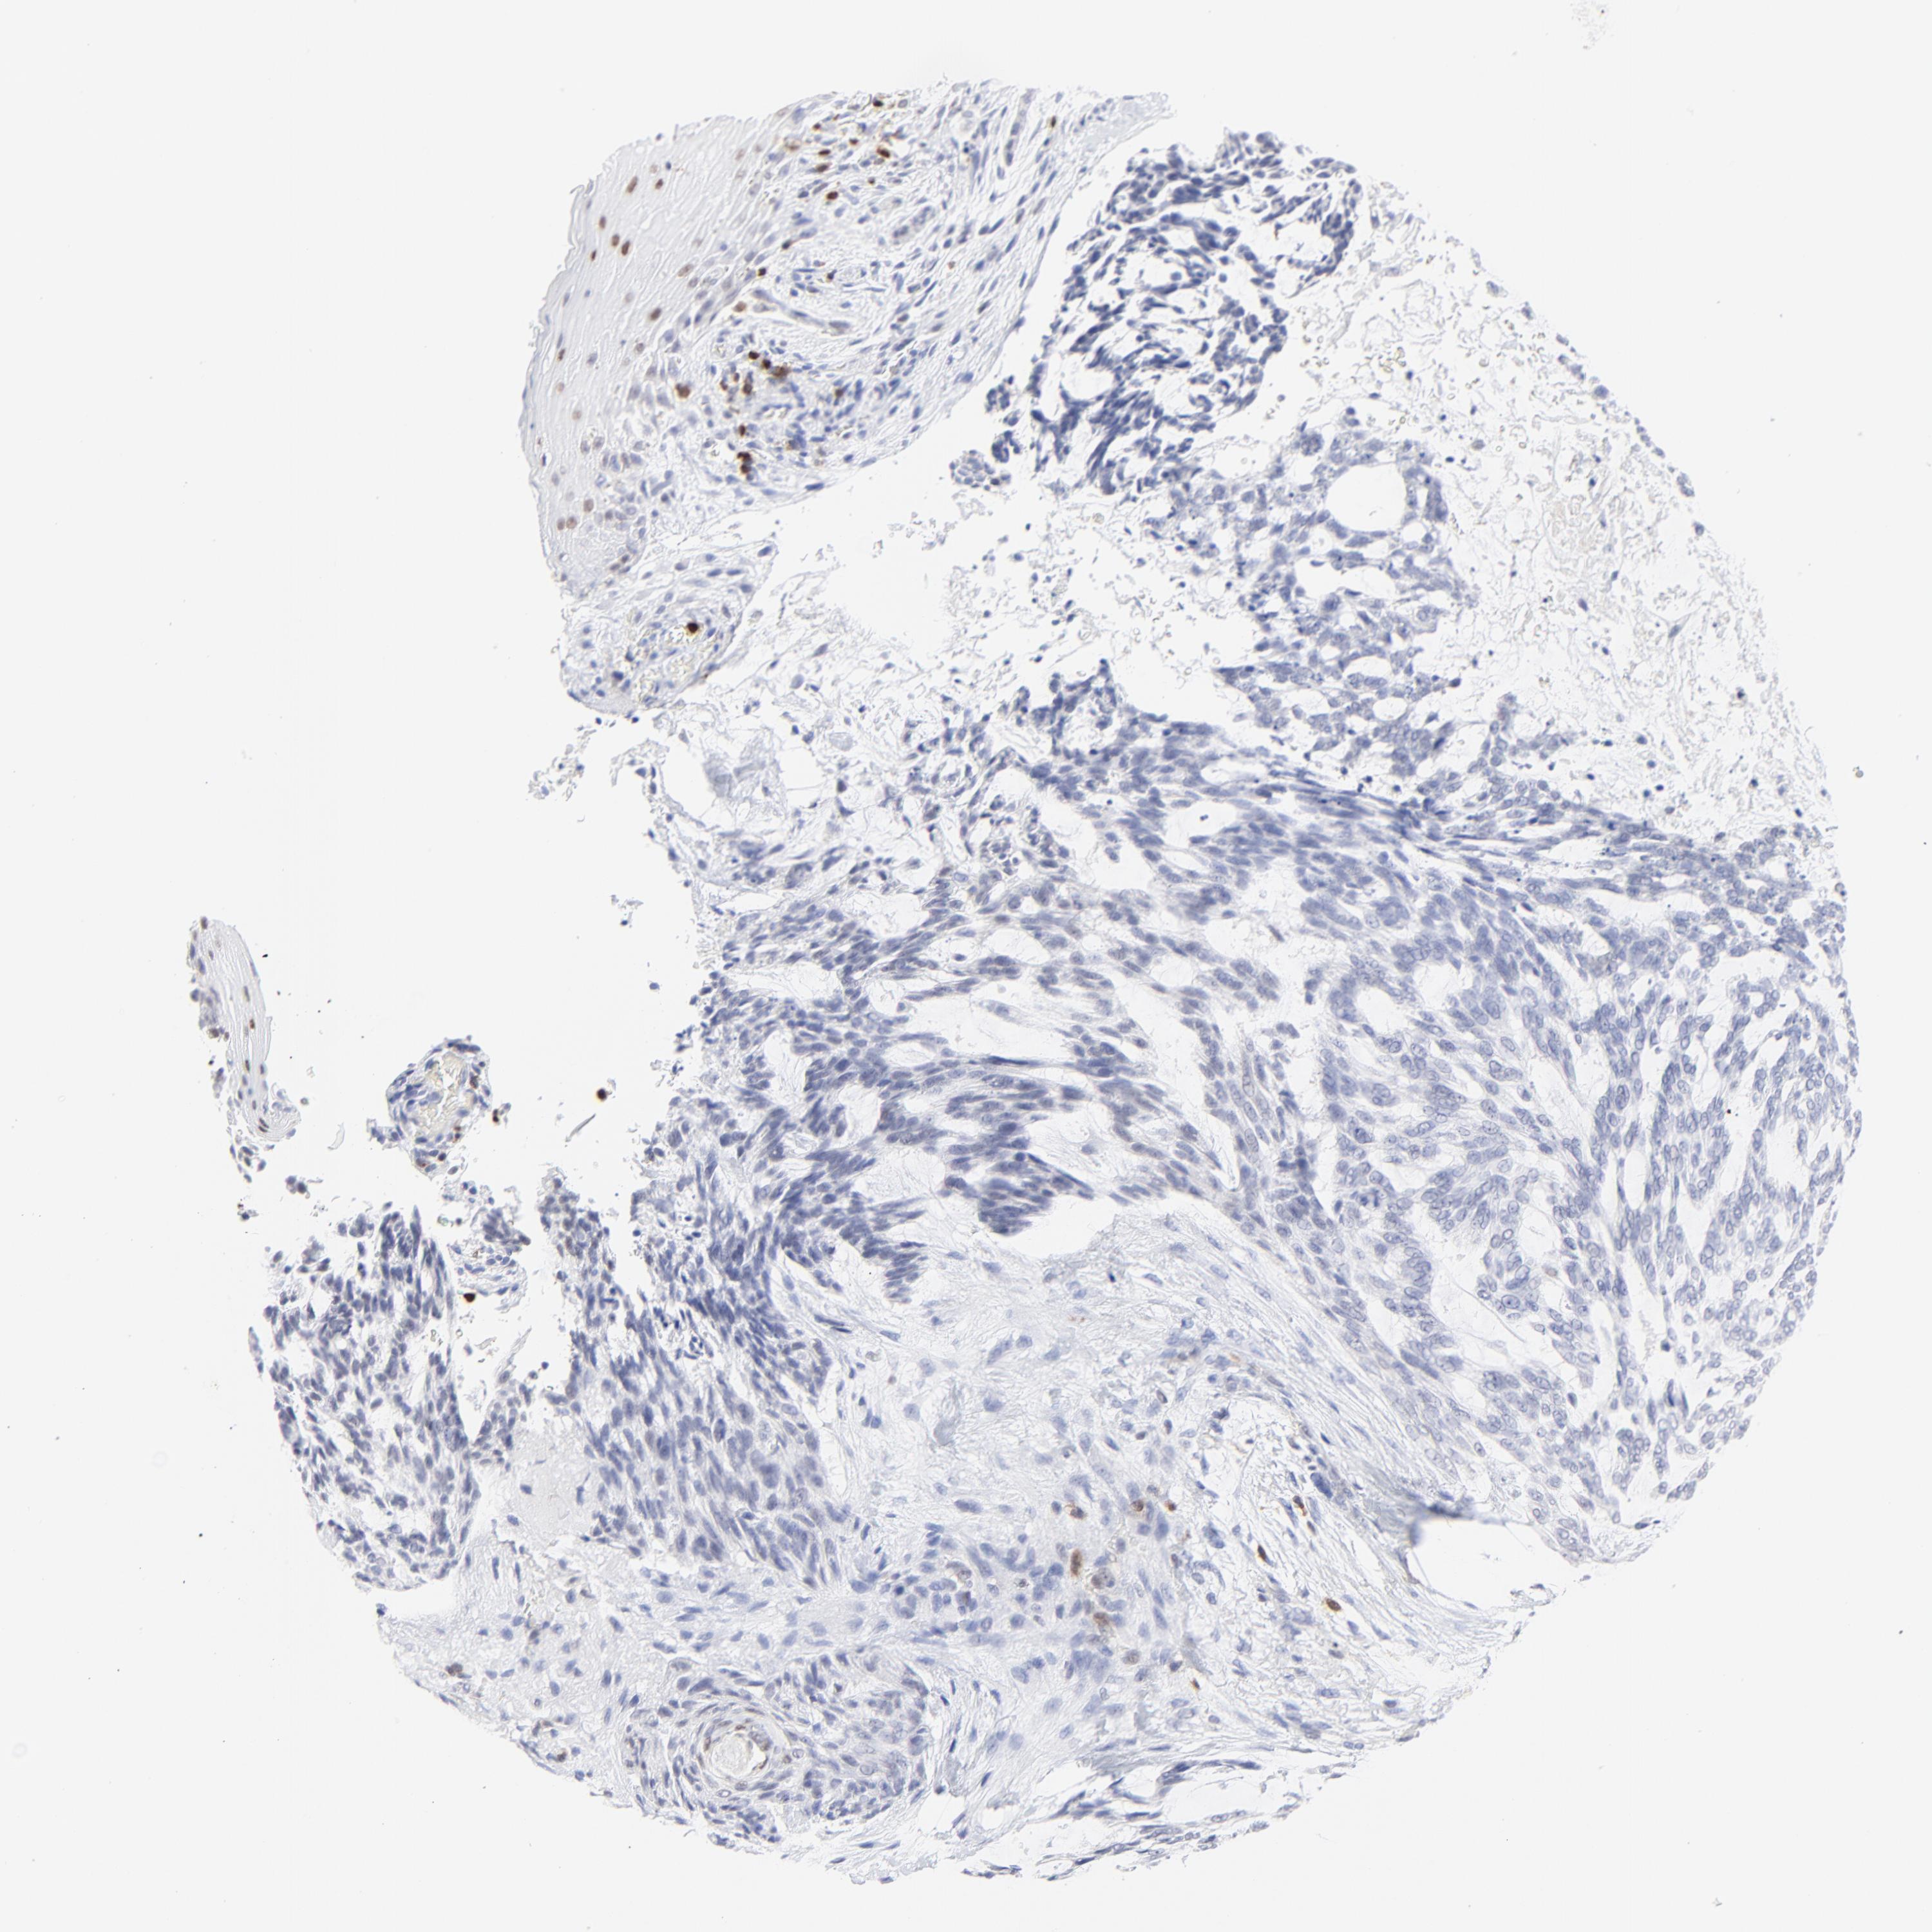

CANCER SKIN CANCER Show tissue menu

Basal cell and squamous cell cancer

SKIN CANCER - Protein expressioni

A mouse-over function shows sample information and annotation data. Click on an image to view it in a full screen mode. Samples can be filtered based on level of antibody staining by selecting one or several of the following categories: high, medium, low and not detected. The assay and annotation is described here.

Each image is clickable and will lead to virtual microscopy that enables deeper exploration of all samples and also displays staining intensity scores, fraction scores and subcellular localization as well as patient and tissue information for each sample.

Antibody HPA003134

Squamous cell carcinoma, NOS

Basal cell carcinoma